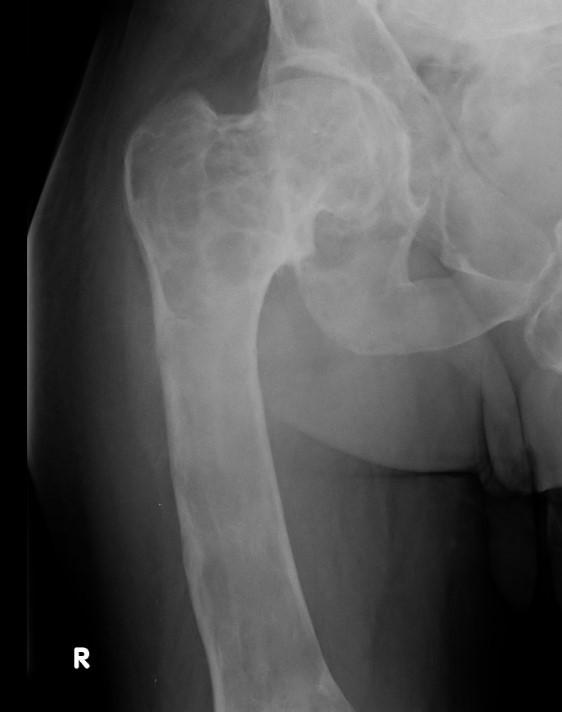

X-ray

Intramedullary lucent diaphyseal lesion with 'ground glass appearance'

- thinned, slightly bulged cortex

- ± endosteal scalloping

- may have angular deformity / bowing

Coxa vara and Shepherd's Crook deformity of proximal femur

- Shepherd's Crook - anterior bowing of femur